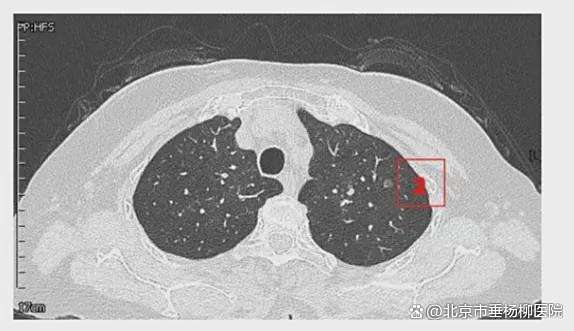

患者女性,71岁,因“发现左肺多发结节2周”入院。胸部CT提示左肺多发磨玻璃结节,较大者位于左肺上叶,呈类圆形,边界清晰,最大直径约9mm。该CT表现高度提示恶性可能。鉴于患者结节数量较多,为减少术中肺组织损伤,术前于CT引导下行经皮肺结节定位术,继而实施胸腔镜下左肺楔形切除术。术中共切除肺部结节6枚。术后病理示:左肺上叶较大结节(4号)为微浸润腺癌,其余5枚结节均为原位癌。患者术后恢复良好,于术后第1天拔除胸腔引流管,第4天顺利出院。

影像资料